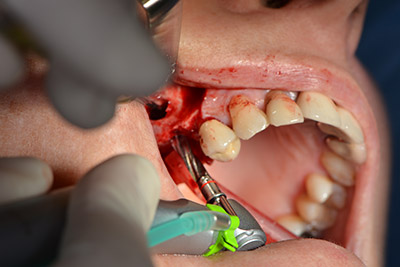

The implant was then placed and the bone built up. In this case, because of the size of the augmentation region, autologous bone chips, harvested with an osseous trap as drilling chips from implantation 16 and fenestration 14, were mixed with bone replacement material.

An absorbable membrane was used as the barrier in the buccal direction and covered the augmentation. Finally, saliva-proof sutures were placed (Fig. 15 to 19).